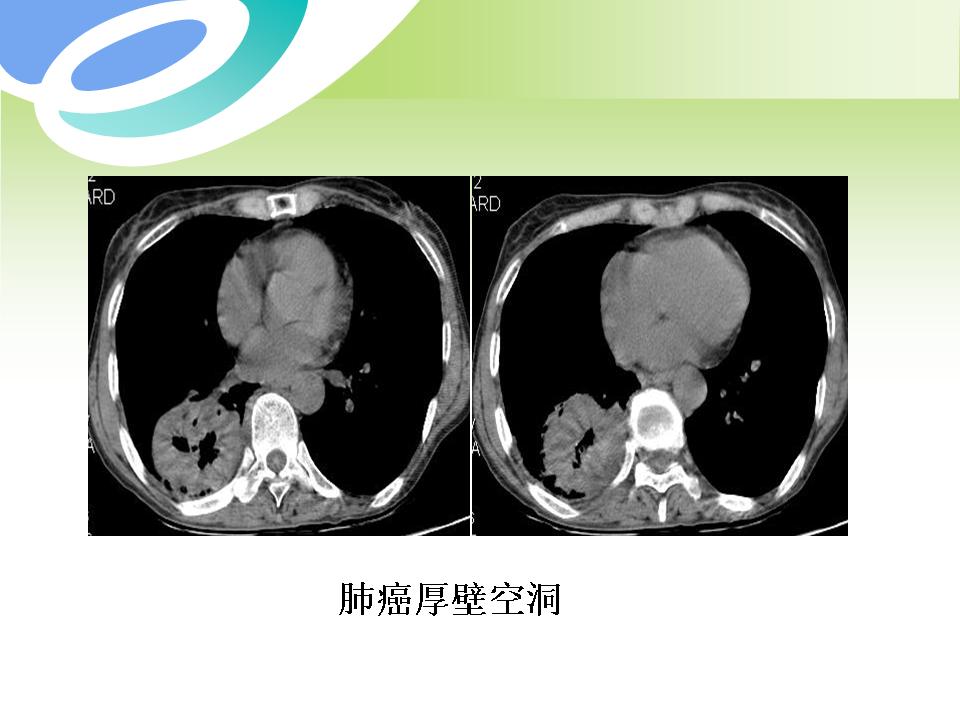

肺部病变的CT基本征象